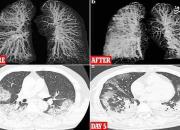

تصویر ریه فرد مبتلا به کرونا

تصویر ریه دو فرد مبتلا به کرونا را ببینید./عکس: dailymail